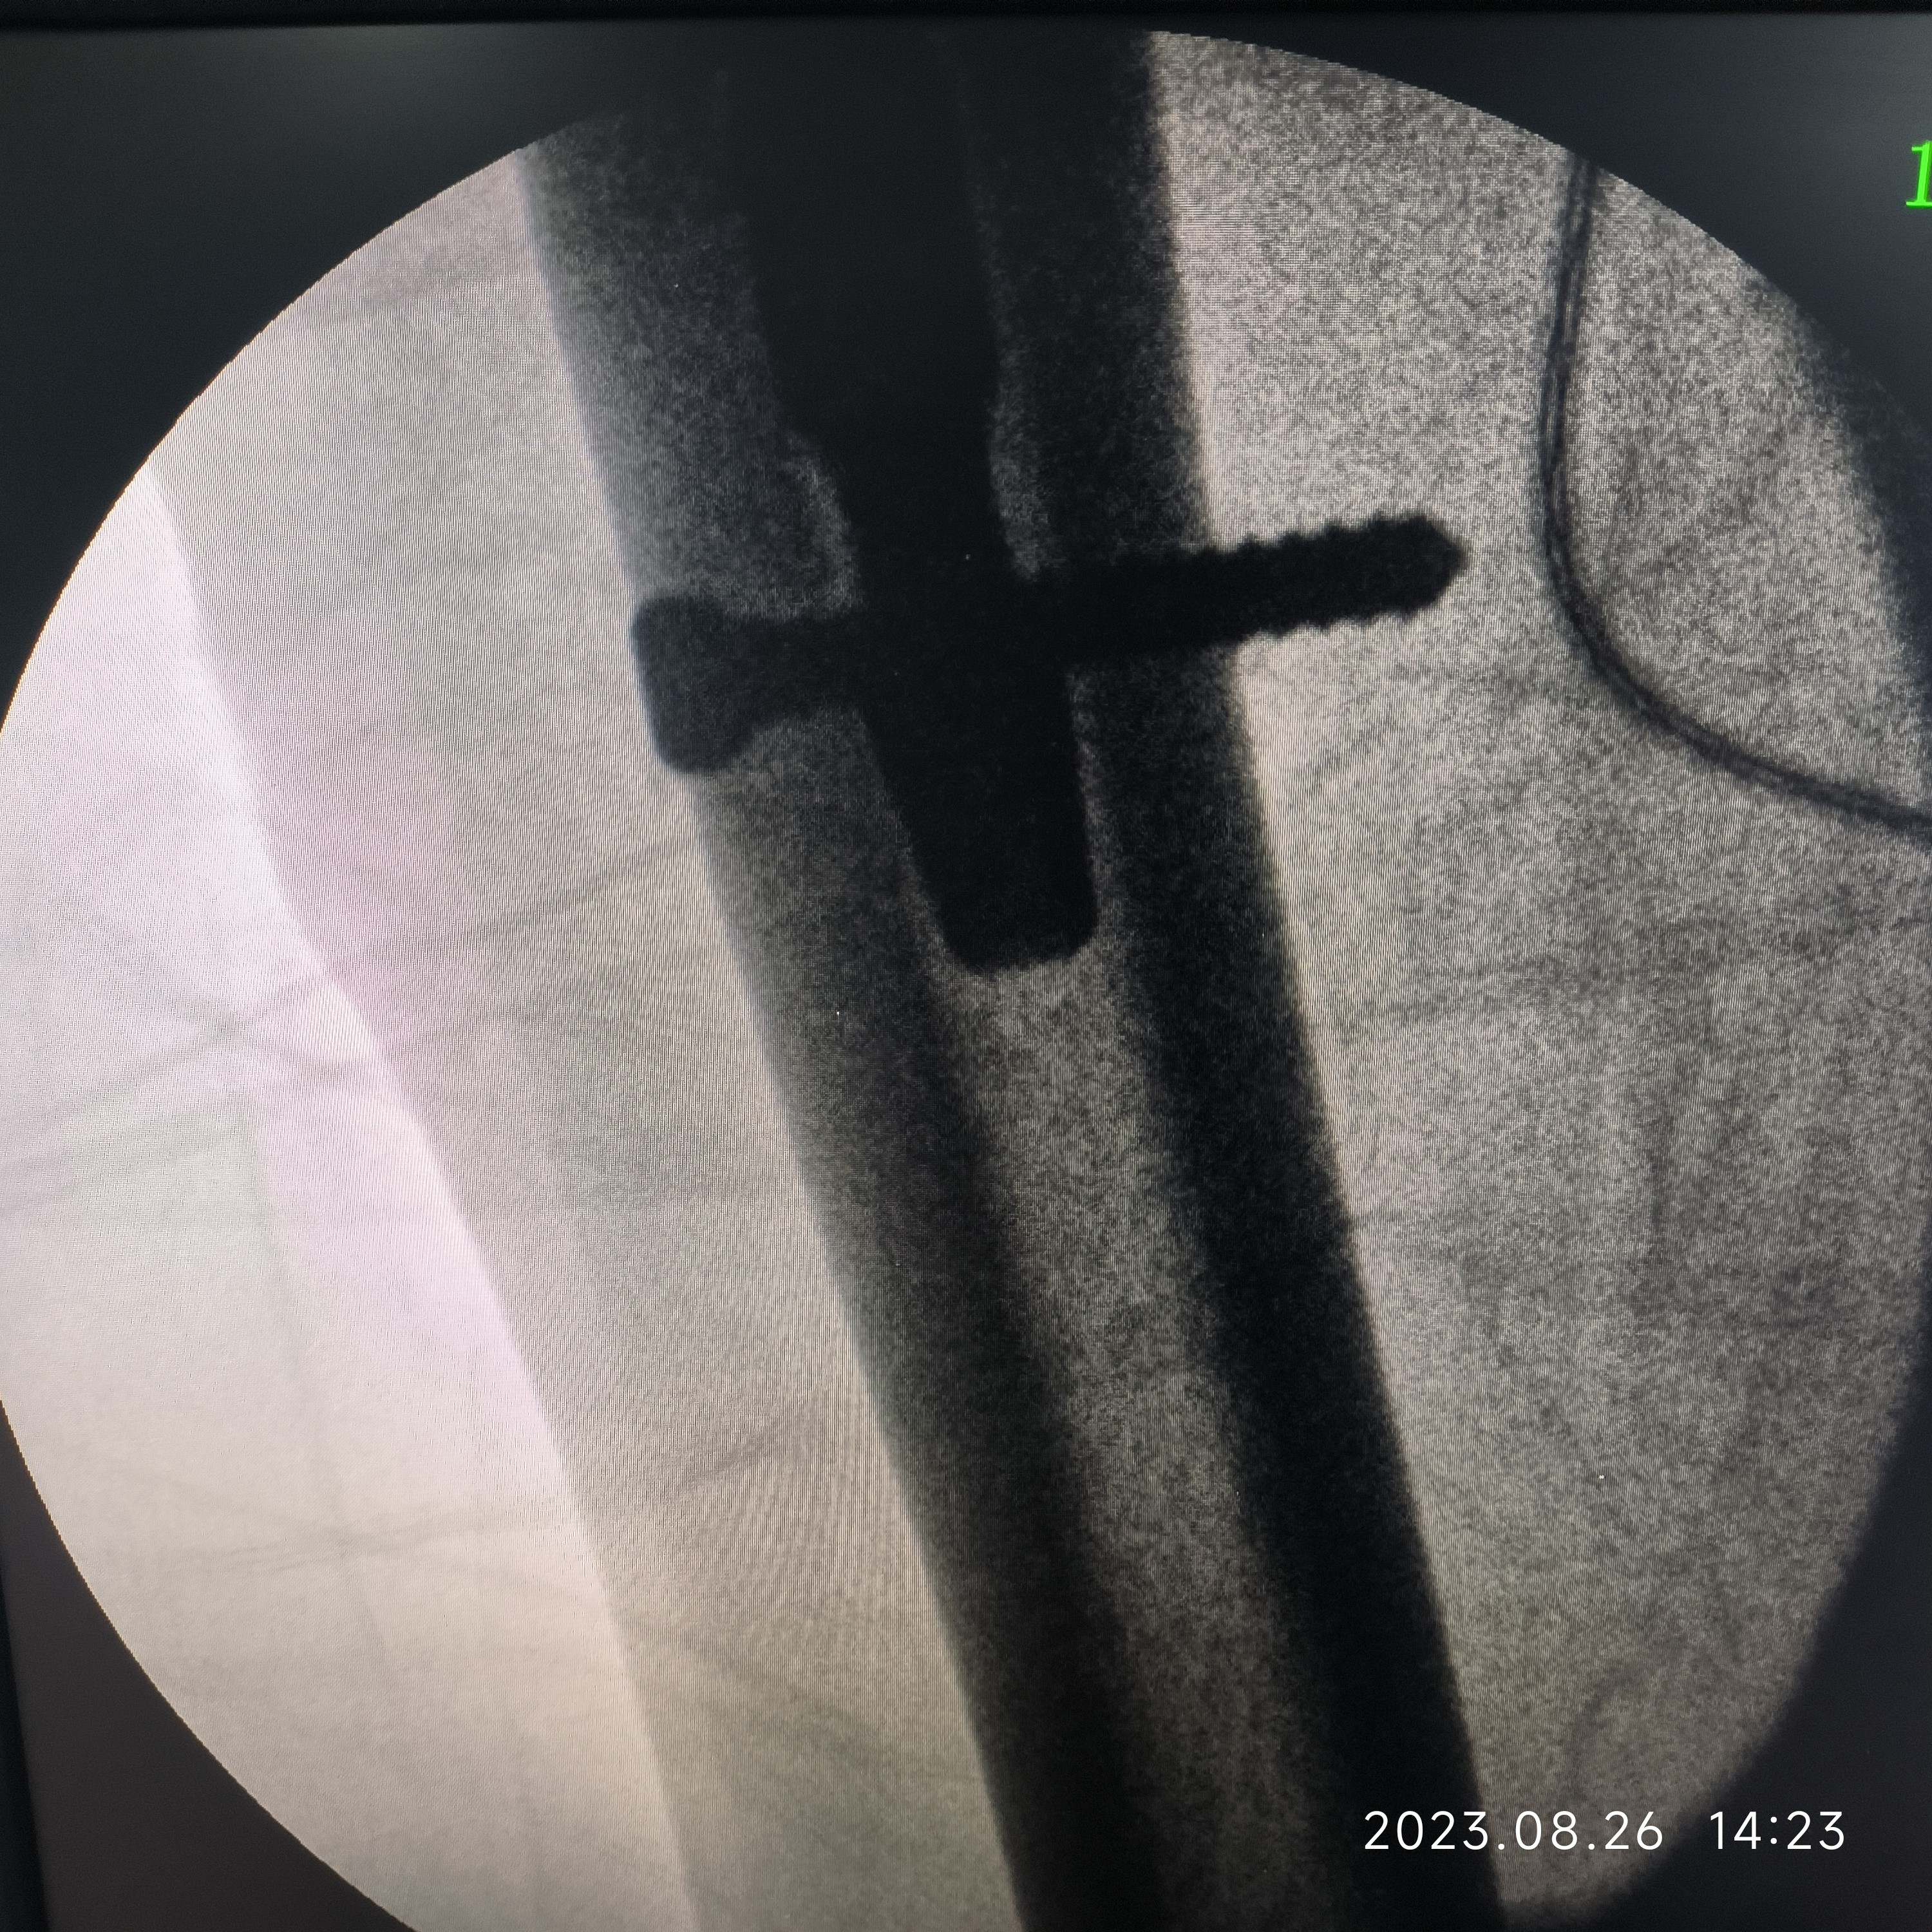

女,80岁,左股骨转子间骨折PFNa。病人营养状况一直不好,胃肠道接受能力非常差,稍微进食油腻基本上一天在10次左右腹泻(常备蒙脱石散、诺氟沙星…),家里老伴身体不好,子女忙都没法在家照顾,强烈要求手术,术前病人血色素6.5g,凝血正常,术中出血700ml左右,低血压报警一次,用了多巴胺后高压维持80mmHg左右,术后输了2U红悬+400ml血浆,第一天复查血色素5.9g,第二天复查血色素6.0g,术后1周复查血色素6.2g……病人精神状态一直还可以……